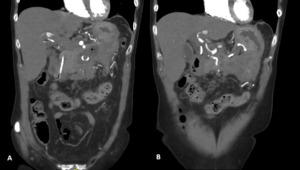

Two weeks later, a repeat CTA demonstrated interval resolution of the previously identified pseudoaneurysms arising from the right, intermediate, and left hepatic arteries. The right and intermediate hepatic arteries were of markedly reduced calibre and tapered shortly after their origins, suggesting proximal arterial occlusion. The absence of contrast opacification within the previously visualised aneurysms was attributed to occlusion of the feeding vessels. Peripancreatic inflammatory stranding had mildly improved, and the previously noted lesser sac collection was no longer visualised (Figure 4).

The patient was managed conservatively with close radiological surveillance with a CT scan at three and nine and 15weeks after this scan. These scans demonstrated no change in the appearance of the hepatic arteries. During this interval, the AXIOS stent and peripancreatic drains were removed without complication.

Final follow-up CT imaging, performed 4.5 months after initial presentation, demonstrated only mild irregularity of the left hepatic artery with a small 2 mm fusiform dilatation. There was minimal residual irregularity along the inferior aspect of the common hepatic artery and a small, thick-walled residual fluid collection measuring approximately 1 cm located between the pancreatic neck and stomach. No new vascular abnormalities were identified (figure 5).